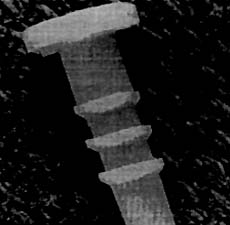

Fig. 7:Dispositivo Biodegradable Canulado Suretac.

El dispositivo SURETAC es un implante absorbentecanulado hecho de polímero poligluconado; sus= dimensiones son 18 mm de largo, 3,2 mm de diámetro, 6,5 mm diámetro de cabeza. La fuerza d retención es similar al DEXON (Dexon, Davis Greck INC, American Cynamid Company, Mana PR USA) y ha sido demostrado experimentalmen que declina rápidamente después del implante de a 4 semanas. Para la colocación se utiliza un taladro canulado, mechas y guías con impactor.

En el caso de una Lesión de Bankart en combinación con una Lesión SLAP se puede utilizar 2 a 3 SURETAC, colocados uno en la posición 11 o'clock, otro en la hora y el tercero en la hora 4 para el hombro derecho, Fig. 7.